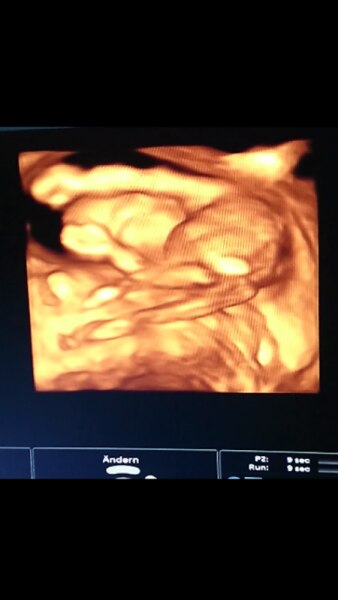

Achja, hab das bild vergessen.. Hab nen Screenshot vom Video gemacht, das bild was er ausgedruckt hat sieht gruselig aus!! Ist von unten, erkennt man alles ganz gut :) hätte aber gern ein schönes Foto gehabt, bin da vom alten fa wohl zu verwöhnt ;)

Glückwunsch. Ich Freu mich so für dich. Crasses Bild. Macht dein Arzt immer 3 d Bilder?

Ja, macht er! Ich habe die US Flatrate gebucht und er meinte, 3D muss ich nicht extra buchen, weil er das eh jedes mal macht :)